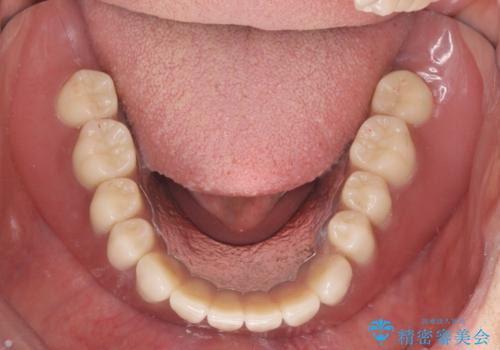

歯が折れている(1DAY インプラント)